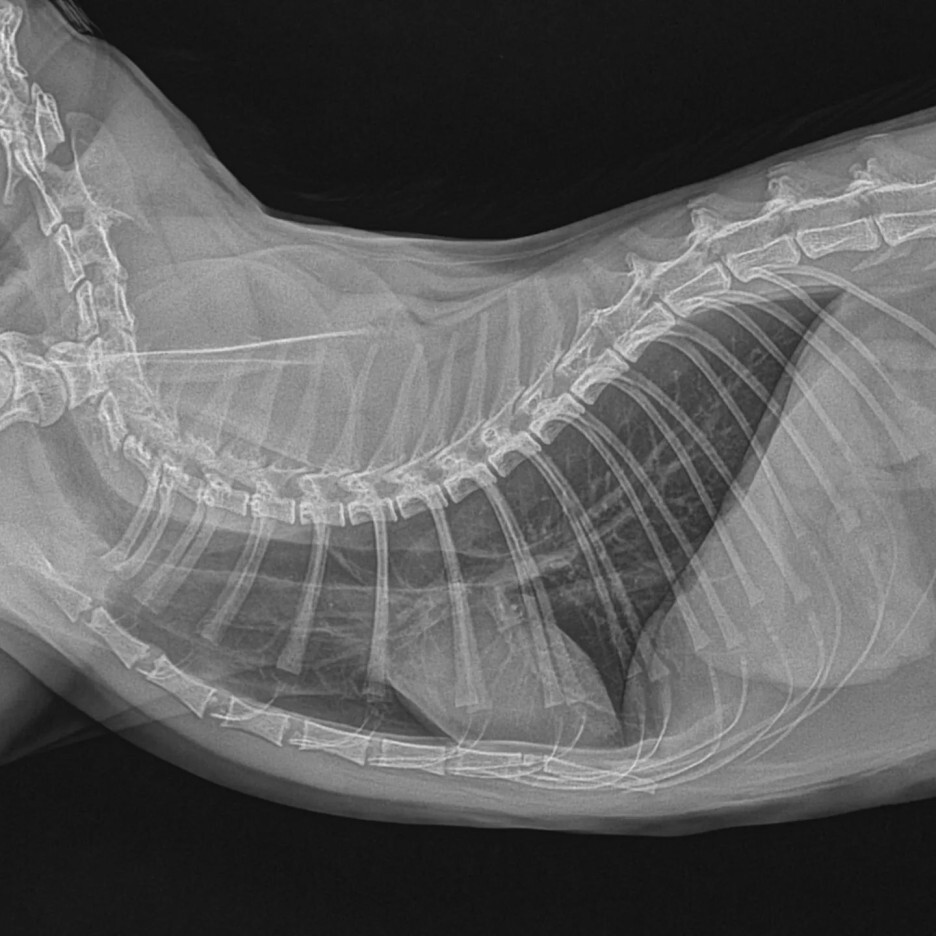

이 엑스레이가 3번째였습니다.. 이때는 진통제를 먹어보고 똑같이 아프다고 보이면

이런 상황일때 두가지 수술 방법이 있다고 합니다.

위에 있는 사진처럼 대퇴골두를 절단하는 방법!!

여기를 절단하면나중에 근육들이 생겨나면서 뼈와뼈를 잡아주어 근육이 골두의 역할을

하기 때문에 괜찮다고 합니다.

그래서 대퇴골두 절골 수술을 하기로 결정했습니다.